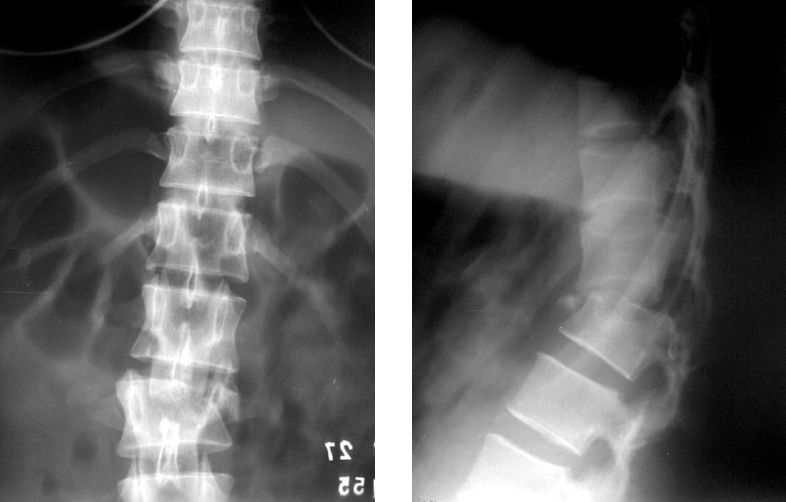

Если все тело стабильно, перелом со смещением следует оперировать немедленно при наличии неврологической симптоматики.